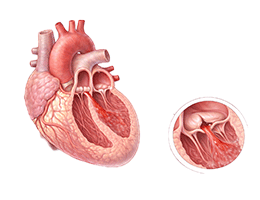

대동맥판역류증 (Aortic regurgitation)

승모판협착증 (Mitral stenosis)

승모판역류증 (Mitral regurgitation)

심장판막질환 (Valvular Heart Disease)

심장판막질환 (Heart Valve Disease)